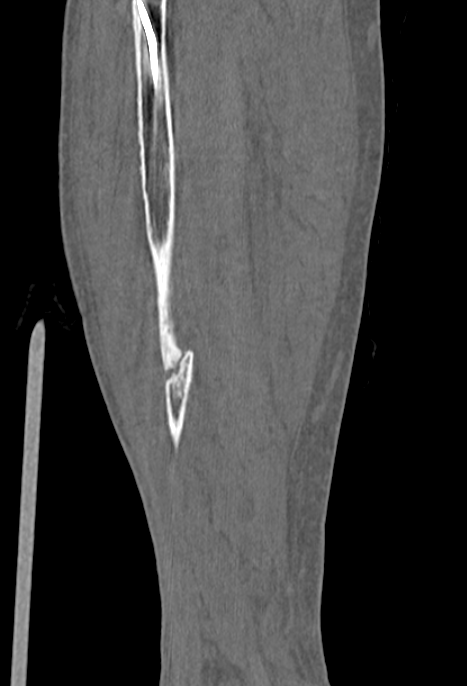

以下は、このCT画像のうちの1枚です。

縦に長い物体が腓骨ですが、この腓骨が折れてつながっていないと考えられるところがあります。つまり、事故から7ヶ月弱経過しても、折れた骨のくっつきが進行していないように見受けられます。

もちろん、この縦断面画像だけで偽関節になっているかどうかを判断できるものではありません。当法律事務所弁護士は、腓骨の骨折部分の縦断面全体を確認しましたところ、どの部分についても腓骨の折れた部分がくっついていないのでは?

と考えました。